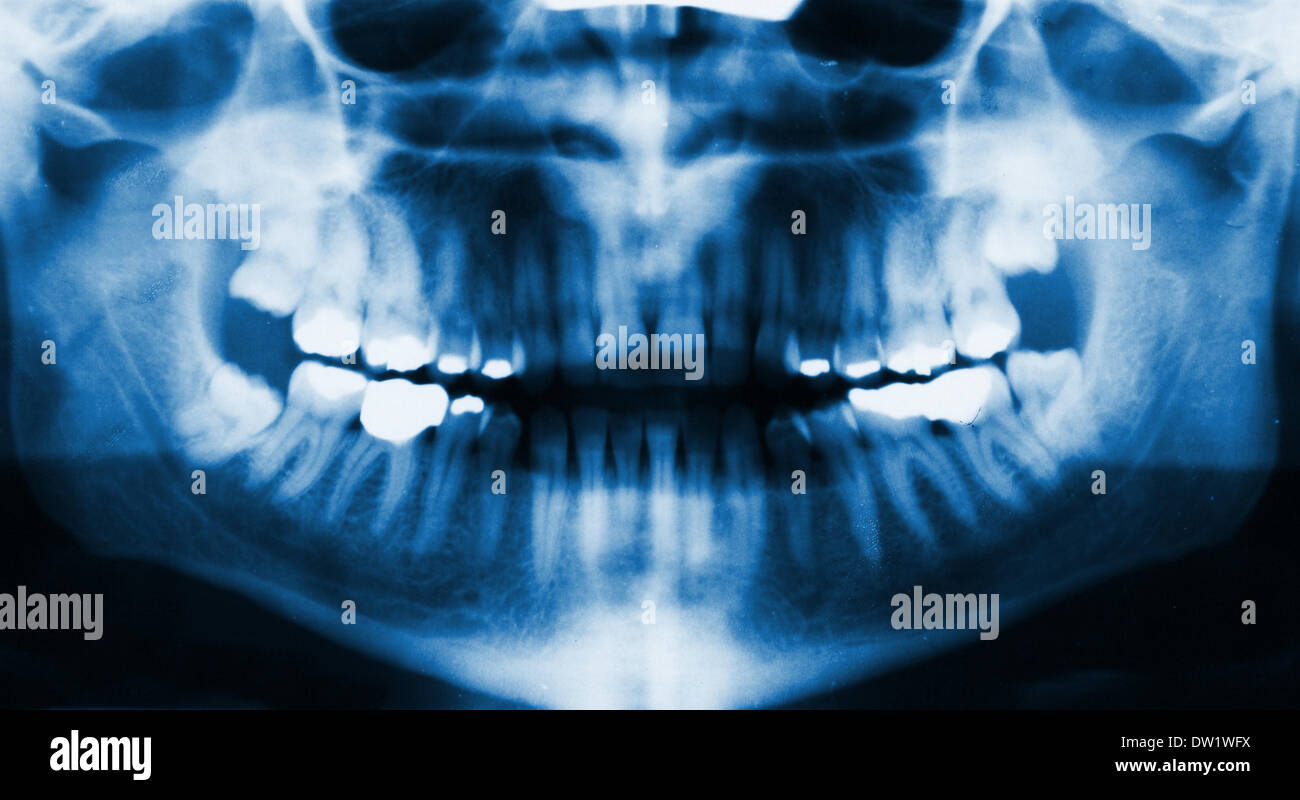

How To Read Dental Panoramic XRay at Carmen Rivera blog Face Anatomy X Ray Relate radiological appearances to clinical features. the occipitomental (om) 4 or waters view or parietoacanthial projection 2 is an angled pa radiograph of the skull, with the patient gazing slightly upwards. Search for subtle injuries and understand their. Understand mechanisms of injury and the likely fractures which may result. There are several standard plain xr views used to demonstrate. Face Anatomy X Ray.